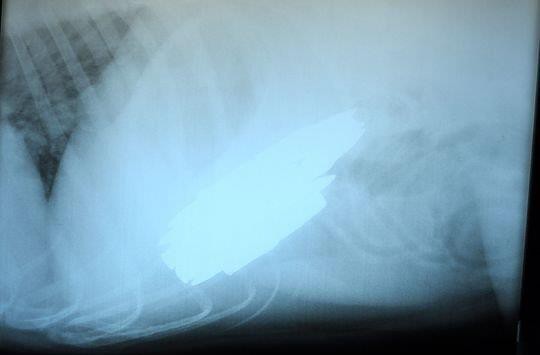

醫生給Benno做了X光,數出了15發子彈,不過Bradfield表示自己數的是17發。醫生Sarah Sexton說:“我們在上學時老師跟我們說課本里講到的東西在現實中也會遇到。可這種情況絕對沒有在課本上出現過,我之前接觸過狗狗吃東西的情況,不過多數都是毛絨玩具。有一次我接診過一隻吞下了助聽器的狗,不過也沒有這個讓人驚訝。”

子彈中含有的鉛和鋅可以很快對狗產生毒性,不過所幸Benno吞下的子彈是銅製的。Sexton給Benno做手術取出了16發子彈,術後的X光掃描又在它的食管里發現了另外兩發子彈,最終也被醫生取出。